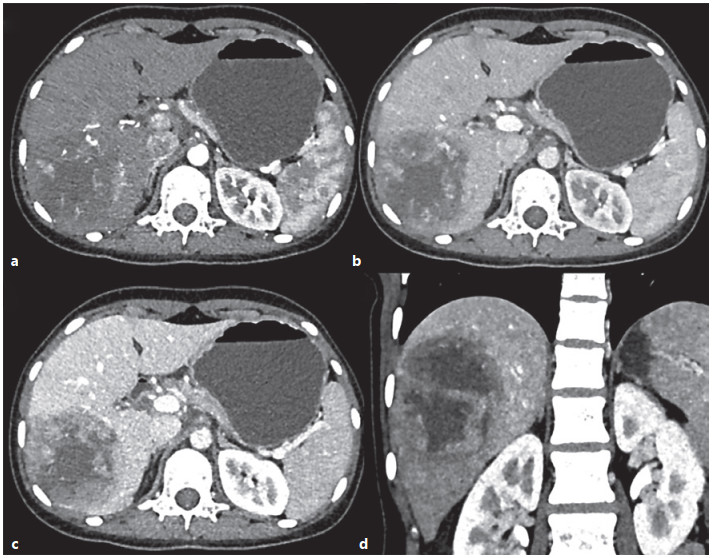

Abstract: Hepatoblastoma (HB) is a rare tumor, but it is the most common primary liver malignancy in children and comprised of approximately 1% of all pediatric malignancies. Mostly, this tumor is sporadic in nature but can show a syndrome association. Upregulation in Wnt/β-catenin pathway can be there in 70–80% cases of HB. Most often present as abdominal mass and has a raised alpha-fetoprotein levels. Distant metastasis usually occurs in the lungs. HB is classified into 2 broad categories: epithelial and mesenchymal type. The majority of HB are epithelial type. The HB must be distinguished from focal nodular hyperplasia, hepatocellular adenoma, and hepatocellular carcinoma, while small-cell undifferentiated HB from the malignant rhabdoid tumor. The histomorphology and immunohistochemistry are essential for the diagnosis of different HB. The neoadjuvant chemotherapy followed by surgery is the mainstay of the treatment. The 2 well-established prognostic factors of HB are stage and histological type. Herein, we report a case series of common and rare histological variants of HB.